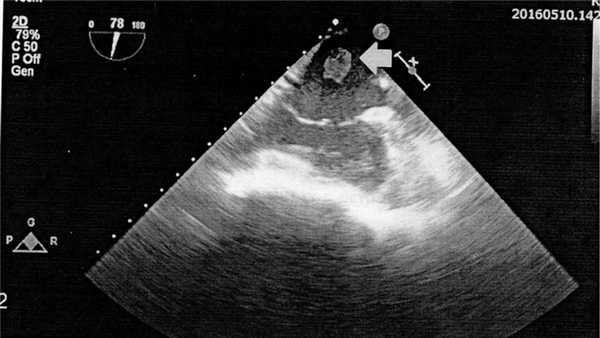

Интраоперационно отмечены следующие особенности. После вентрикулотомии, выполненной через верхушку ЛЖ, выявлено новообразование продолговатой формы размером 2,5×7,0 см, исходившее из его верхушки. Оно частично фиксировалось к МЖП и боковой стенке Л.Ж. Новообразование удалено единым блоком (рис. 3). ЛЖ ушит двухрядным швом на тефлоновых прокладках. При контрольной ЧПЭхоКГ был выявлен фрагментированный участок тромба в левом предсердии (рис. 4). Выполнена левая атриотомия параллельно межпредсердной борозде. Фрагментированный участок тромба размером 1,5×2,0 см удален. После снятия зажима с аорты и согревания больного возникла фибрилляция желудочков; однократной дефибрилляцией восстановлен С.Р. Повторная контрольная ЧПЭхоКГ продемонстрировала отсутствие внутриполостных новообразований, уменьшение КДО ЛЖ и КСО ЛЖ до 130 и 69 мл соответственно, увеличение ФИ ЛЖ до 46,9%.

Рис. 4. Чреспищеводная ЭхоКГ больного А., 43 лет. Диагноз: состояние после удаления тромба левого желудочка, фрагментированный участок тромба в левом предсердии.